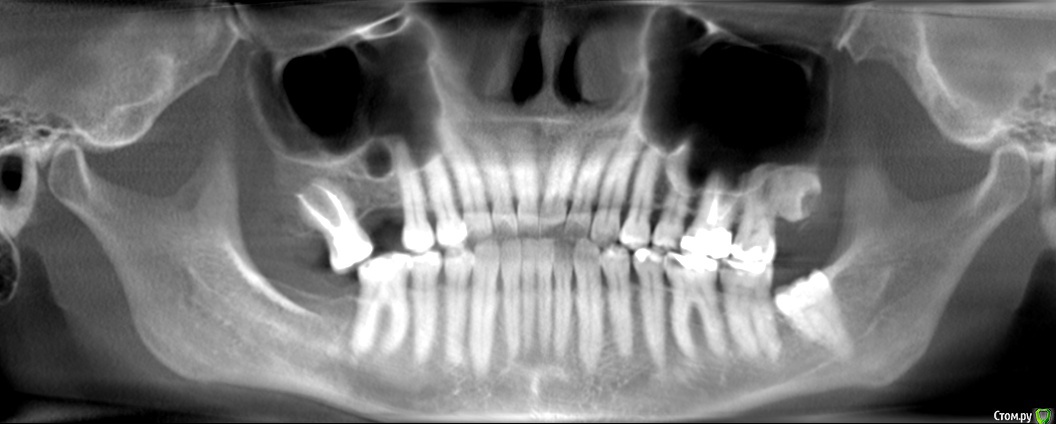

wladdX Опубликовано 27 февраля, 2019 Поделиться Опубликовано 27 февраля, 2019 (изменено) Скриншоты Сколько успел Изменено 27 февраля, 2019 пользователем wladdX Ссылка на комментарий

red_butler Опубликовано 27 февраля, 2019 Поделиться Опубликовано 27 февраля, 2019 соустье нужно посмотреть, но предварительно - не вижу препятствий для проведения открытого синуслифта Ссылка на комментарий

wladdX Опубликовано 27 февраля, 2019 Поделиться Опубликовано 27 февраля, 2019 Похоже, я загрузил скрины другого пациента (на диске записаны 2 исследования), исправляюсь. Ссылка на комментарий

kramer Опубликовано 27 февраля, 2019 Поделиться Опубликовано 27 февраля, 2019 Закрытый синус-лифт + 10 мм имплантат Ссылка на комментарий

red_butler Опубликовано 27 февраля, 2019 Поделиться Опубликовано 27 февраля, 2019 8 мм имплант и закрытый синус без графта Ссылка на комментарий

колесников Опубликовано 3 марта, 2019 Поделиться Опубликовано 3 марта, 2019 У вас речь идёт об одном импланты в области 16. Одиночный короткий Имплант не рекомендуется ни одним из производителей имплантов. Открытый синуслифтинг не показан из за особенностей строения пазухи в этой области,показан закрытый. Так же рекомендовал бы Астра тек,4.5х9. А также:дистализация 17го и имплантация в области 47.. либо удаление 17го,имплантация 17,16,47 Ссылка на комментарий